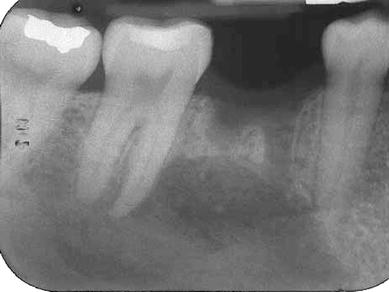

A 42-year-old Caucasian female presented with extreme pain of the right mandible and paresthesia of her right lower lip from the commissure to the midline. The patient reported that sudden severe pain began 4 months earlier in the right mandible. Consultation with a private dentist for the pain resulted in the initiation of endodontic therapy for tooth #30. Subsequent to the completion of root canal treatment on tooth #30, the pain increased and the paresthesia began. Both the pain and paresthesia were non-responsive to a short course of steroids and antibiotics. Tooth #30 was extracted 1 month prior to presentation. Following the extraction, the pain and paresthesia worsened and a “swishing” sound developed in her right ear. Evaluation by otolaryngology was negative. Intraoral and extraoral examinations were unremarkable except for the right lower lip paresthesia. Panoramic (Fig. 1), occlusal (Fig. 2) and periapical radiographs (Fig. 3) were taken at the time of presentation.

Fig. 3

Periapical radiograph